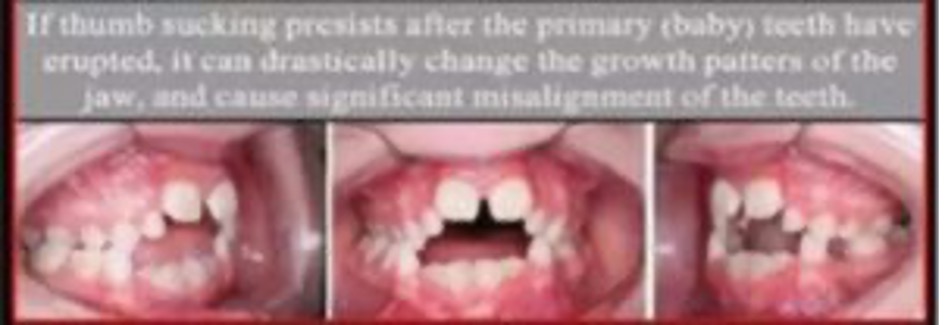

Thumb-Sucking or Prolonged Bottle Use: Habitual sucking or bottle use after the adult teeth have come in can cause problems for the development of the jaw placement and the primary teeth (adult teeth). This change in growth patterns can cause malocclusion of the teeth as shown below. In addition, with the change in growth pattern then a change in the jaw line can be seen. The tongue can also lose its appropriate position and effect the way food or liquids are swallowed.

Malocclusion: Misalignment of the teeth causing crowding or no space for new teeth to erupt. This creates a poor bite.

Tongue Thrusting: Habitual pushing forward of the tongue between the upper and lower teeth while swallowing or talking. This is improper usage of the tongue as it should push against the gum above the back of the upper front teeth.